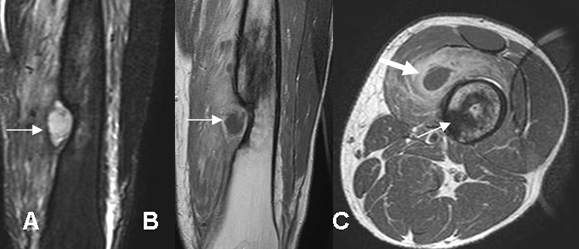

Fig 39. Osteomielitis subaguda.

A: RM coronal en STIR y B: RM coronal en T1 con contraste. Defecto óseo en la tibia ocupado por colección líquida, cuyos bordes realzan con el contraste y corresponde a absceso de brodie.

C: RM axial en T1 con contraste. Adicional al absceso de brodie (Flecha delgada), se encuentra colección de tejidos blandos. (Flecha gruesa).